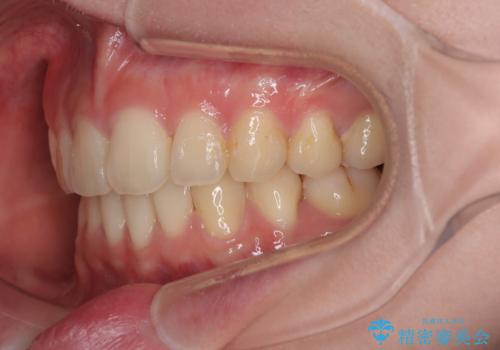

深い咬み合わせは上顎前歯を引っ込ませる大きな障害となるため、咬み合わせの改善が非常に重要となります。やや期間はかかりましたが、当初狙った通りの仕上がりで治療を終えることができました。